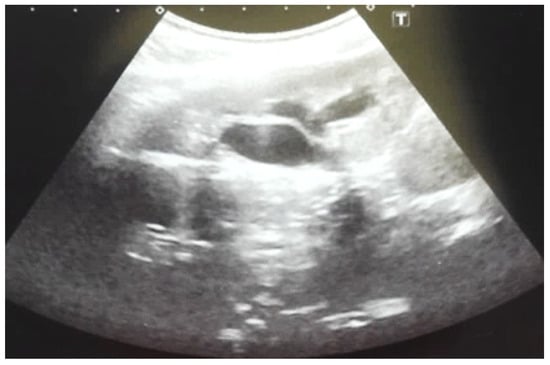

Our experience with congenital malformations of the urinary system refers to the following clinical case (Figure 2, Figure 3, Figure 4, Figure 5, Figure 6, Figure 7, Figure 8 and Figure 9). In the first case, during pregnancy, the 21-week ultrasound determined bilateral renal pyelectasia. The fetus had hydronephrosis on the right; at 31 weeks, it had bilateral hydrocalconephrosis; and at 32 weeks, bilateral pyelectasia. It suffered premature birth at 36 weeks, with complicated anomalies of the forces of contraction, prolonged birth, and birth weight of 2200 g. Postnatal ultrasonography was supplemented by intravenous urography, and bilateral hydronephrosis was determined. Hydrocalconephrosis on the left was discovered. The complete diagnosis was established: congenital renal malformation; bilateral pyelectasia; bilateral hydronephrosis; hydrocalconephrosis on the left; and severe reduced glomerular filtration rate (GFR), GFR > 2SD below mean.

Figure 6. Ultrasound of the postnatal urinary system 10 days after birth. Hydronephrosis on the right.